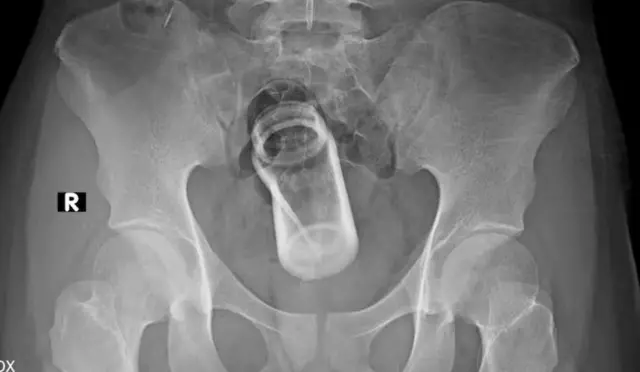

مقعد کے راستے سے بھی فارن آبجیکٹ داخل ہوسکتے ہیں۔ اس شکایت کے ساتھ ہسپتال آنے والے 66 سے 85 فیصد مرد ہوتے ہیں۔

جنسی خواہش سے لے کر قبض میں ریلیف تک، مقعد کی نالی میں کسی چیز کو داخل کرنے کی کئی وجوہات ہوسکتی ہیں۔ ان چیزوں میں سیب، بینگن، برش، قلم، گاجر، مچھر مار سپرے کے کنٹینر، ڈیوڈرنٹ (جسے سرجری کے ذریعے نکالنے کے دوران آگ لگنے کا خطرہ بھی ہوتا ہے)، گلاس، کولڈ ڈرنگ کی بوتل اور بیس بال شامل ہیں۔ سب سے زیادہ حیران کن چیز شاید پورا ناریل ہے۔

مقعد کی نالی کے باہر وہ پٹھے ہوتے ہیں جو پاخانے کو اندر رکھنے اور باہر نکالنے میں مدد کرتے ہیں۔ کسی فارن آبجیکٹ کے داخلے سے ان میں کھچاؤ پیدا ہوتا ہے اور ان میں اتنی قوت نہیں رہتی کہ وہ اُس چیز کو باہر نکال سکیں۔ ڈاکٹروں کو اکثر ان چیزوں کو باہر نکالنے کے لیے باقاعدہ سرجری کرنی پڑتی ہے۔